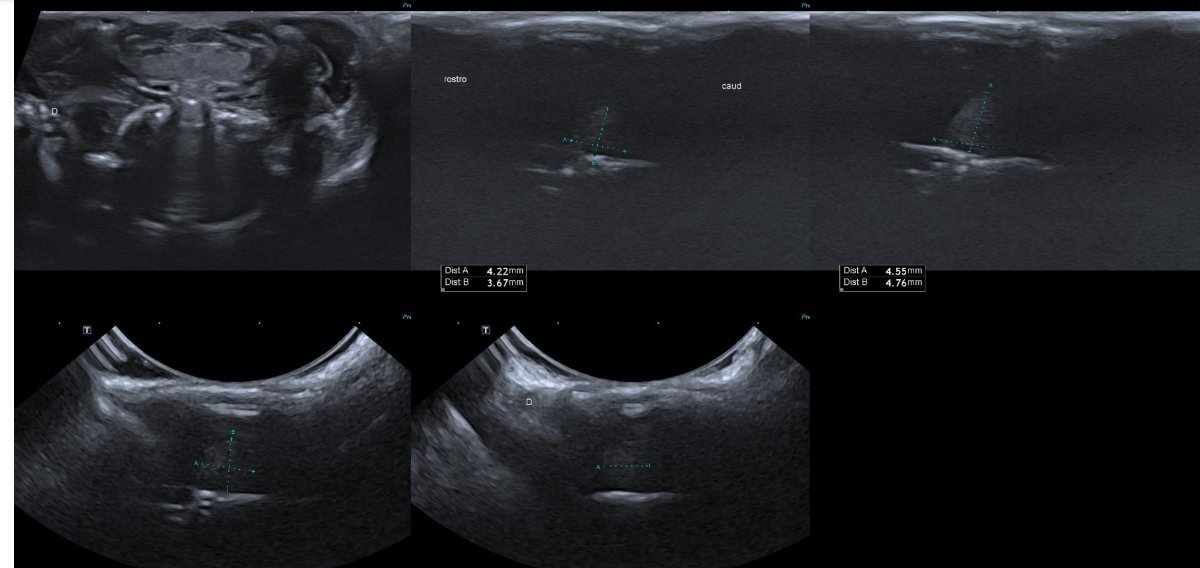

Alors, voici l'échographie du jour ! Première fois que je suis aussi contente de voir une tumeur :transpire: (Bon, j'avais pas de doutes, donc c'est surtout que je suis contente d'avoir la validation qu'ils réussissent à les voir)

Screenshot_20260313-172406_Drive.jpg

Avec les radios ça commence à aller, mais sur les échos je vois jamais rien, c'est où que tu vois une tumeur ? (Pour que je puis comparer avec les échos d'Alcyone :siffle:)

Je pense que c'est là où l'echographiste a fait des petits pointillés verts pour la mesurer !

Merci @Vazaha, c'est génial de savoir que ça marche et de pouvoir voir les images <3 j'espère que le traitement va aider Graine le plus longtemps possible.

Ah ok, donc la différence c'est que sur celles d'Alcyone la taille est différente et c'est plus noir (enfin j'imagine :transpire:)

Oui, c'est ça !

Après j'avoue que je serai incapable de me repérer seule, autant les radios ça va, autant les échos c'est compliqué ^^'